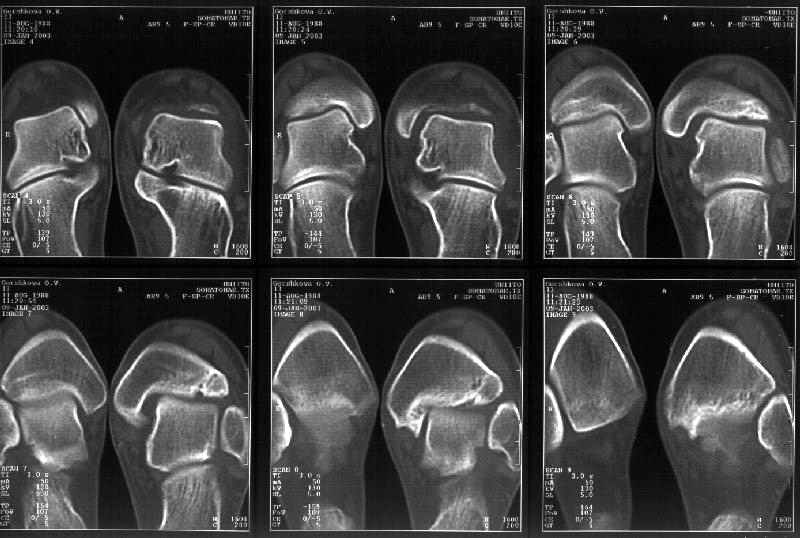

Здесь 4 среза, начиная от основания лодыжки и проксимальнее. Где, по Вашему мнению, проходит линия перелома, отделяющая переднюю часть внутренней лодыжки от большеберцовой кости? Заранее спасибо.

Сегодня пациентке сделали сравнительную КТ. А ксиальные и Фронтальные срезы приложены. Ваше мнение?

Фронтальные

Аксиальные

На КТ я попытался изобразить скромными своими способностями (А)- место перелома, (С)- нормальный суставной зазор меж тараном и тремя его маллеолами. (В)- образовавшийся в результате перелома широкий раза в три зазор, позволяющий, по-моему, сублюксацию тарана при ходьбе. В свете данных КТ, критически важных, я бы предложил вертикальную остеотомию места перелома

задне-внутренним подходом и фиксацию мед. маллеола прижатым к тарану с помощью тонкого compression screw. После этого гипсовый сапожок и немедленное расхаживание ноги.